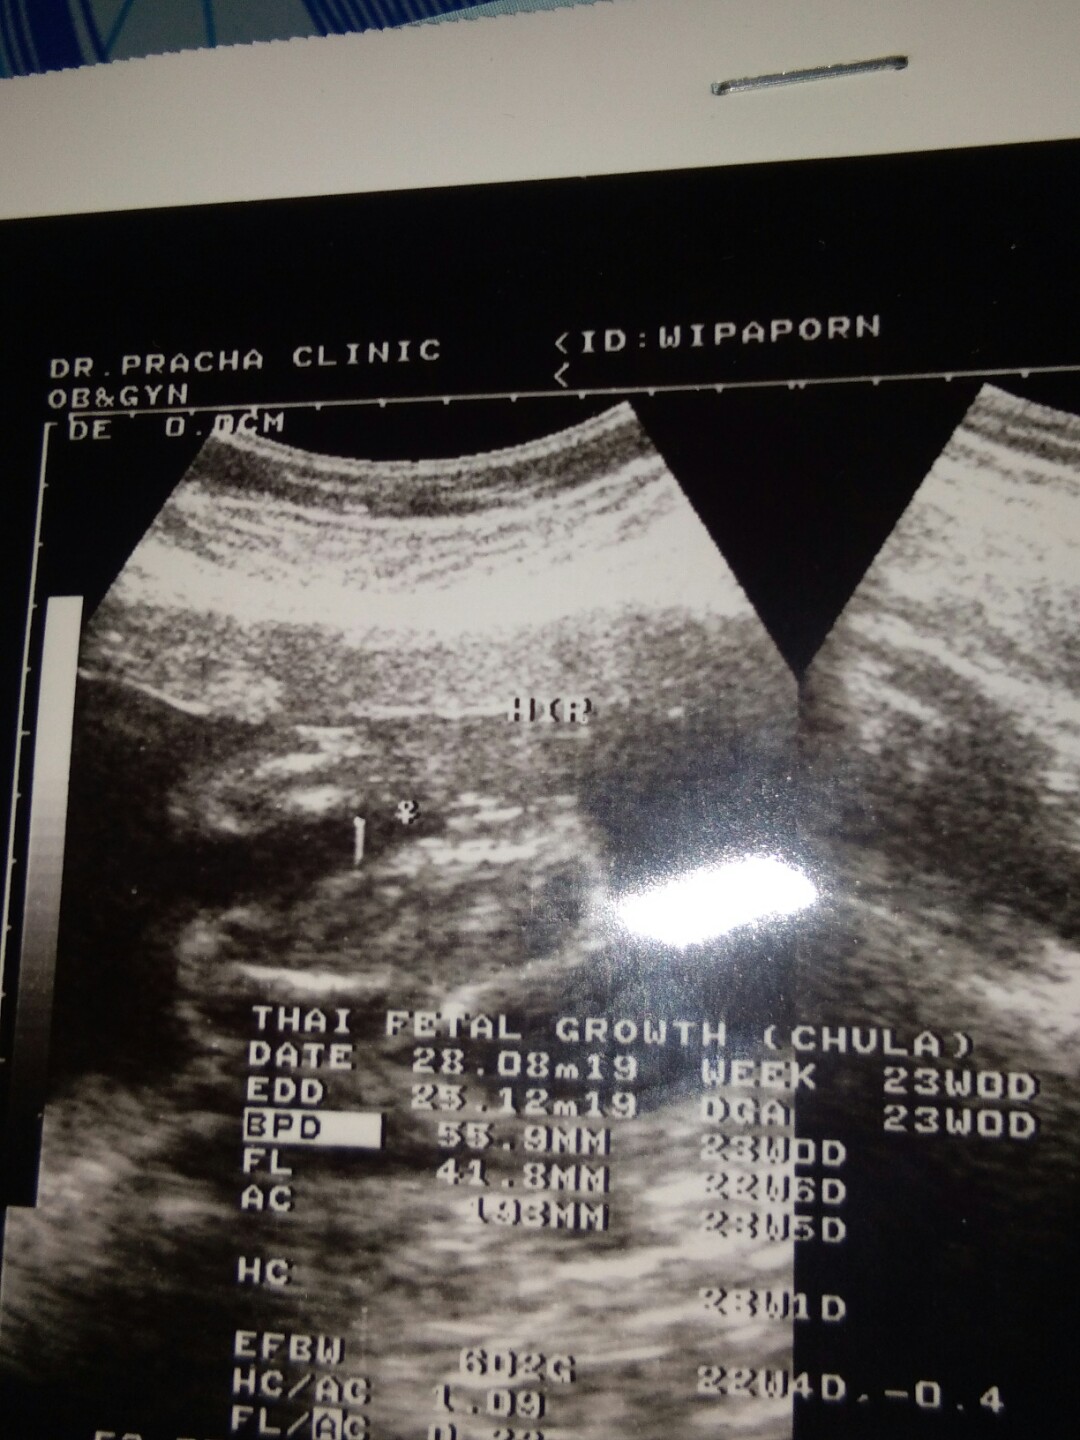

โชว์ผลซาวด์กันค่ะ

คุณลุงหมอบอกมีกลีบ?ใครมีกลีบ ใครมีแท่ง ลงมาอวดกันจร้า

มีกลีบเหมือนกันจ้า

บ้านนี้กลีบค่ะ